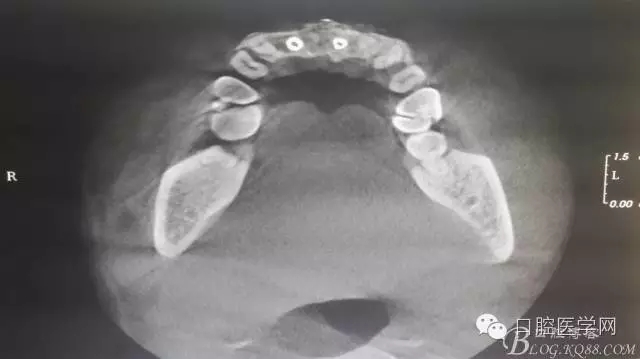

植入種植體左側3510,右側4010,植骨Bioss,蓋膜Cytoplast。骨膜減張垂直褥式縫合加間斷縫合。

之所以選擇Bioss是考慮其降解速度較慢,種植體接觸大面積為自體骨,Bioss可以很穩(wěn)定的緩慢吸收逐步引導骨再生。